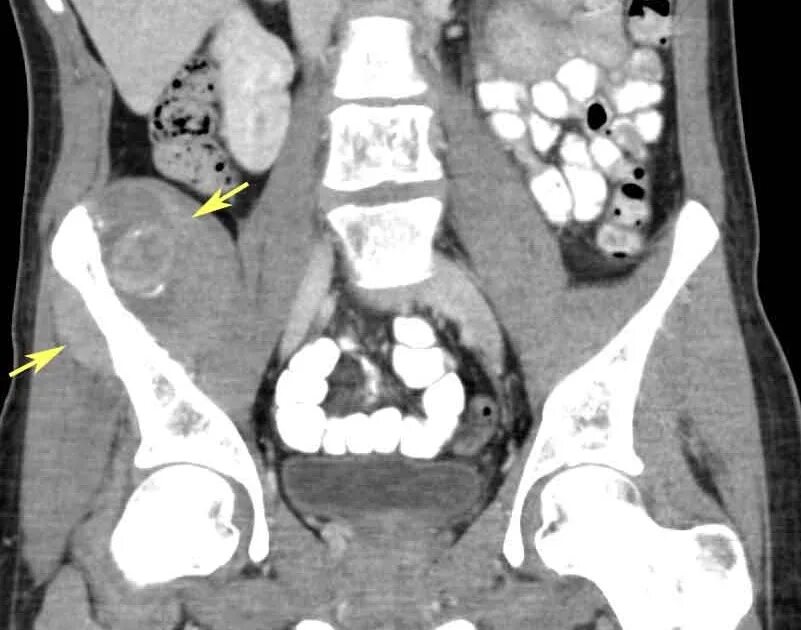

Метастазы в крестце